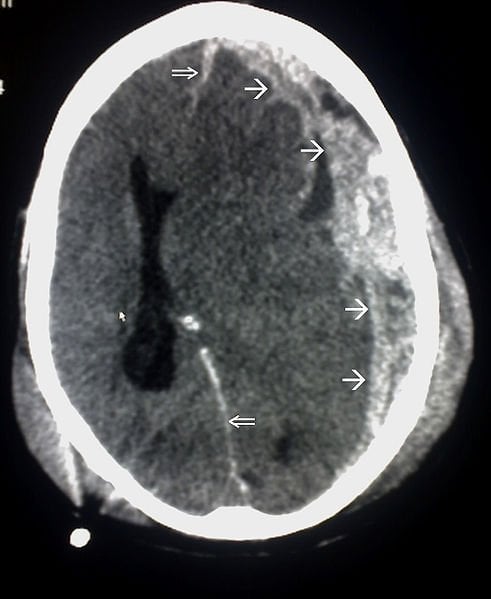

Cellular damage in the brain after traumatic injury can cause severe, ongoing neurological impairment and inflammation. Few pharmaceutical options exist to treat the problem. About half of patients with severe head injuries need surgery to remove or repair ruptured blood vessels or bruised brain tissue.

Image Source: The image is credited to Wikimedia Commons user Glitzy queen00 and is in the public domain.